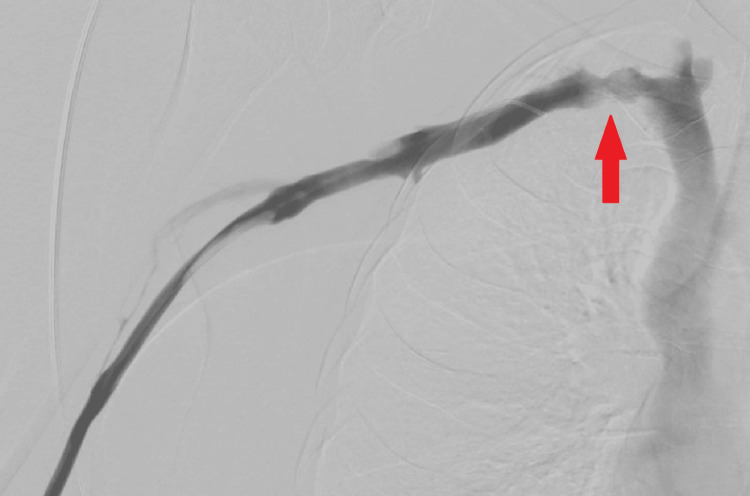

We discuss the case of a 36-year-old woman who presented with persistent right upper limb swelling and pain. A previous negative D-dimer (434 µg/L (normal range <500 µg/L)) resulted in an inappropriate discharge, despite a significant past medical history. The patient was sent for a right upper limb ultrasound Doppler scan due to persistent pain, and a clot in the right supraclavicular subclavian vein was observed, confirming the diagnosis of Paget-Schroetter syndrome (PSS). The clot was successfully removed under the vascular team in Cardiff without any post-op complications. The literature review demonstrates that PSS should be suspected mostly on a clinical basis; the literature does not support the use of a D-dimer to support a suspected upper limb deep vein thrombosis (DVT), as this could delay vital treatment for the patient, as demonstrated in this case.